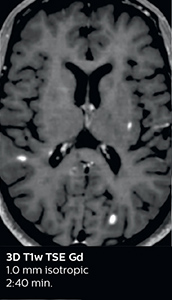

Fast MS protocol with optional sequences

The abbreviated MS protocol for brain is only around 9 minutes, so in case of suspected multiple sclerosis, one or two more advanced sequences may be added, such as PSIR (phase sensitive inversion recovery) or susceptibility-weighted sequences to help us make more confident diagnoses in these inflammatory cases.

In this example, the optional 3D multishot susceptibility weighted sequence with 0.6 mm isotropic voxels is 2 lesions with a central vein sign (arrows) and one lesion with a phase-rim sign (arrowhead). The total scan time, including SmartBrain and axial PD/T2 3mm, is 11:10 min. and is 18:30 min. with the optional 3D PSIR and 3D SWI multishot included.

3D TFE T1

3D FLAIR

DWI image

3D T1w TSE Gd

3D PSIR

3D SWI